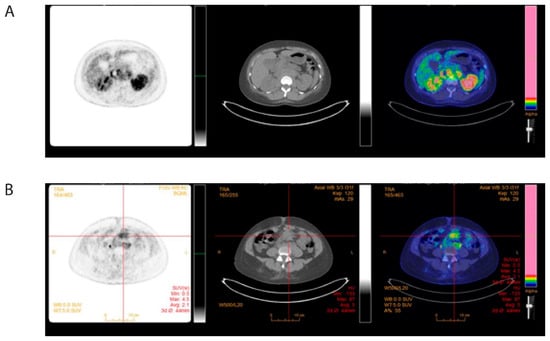

2. Case Presentation